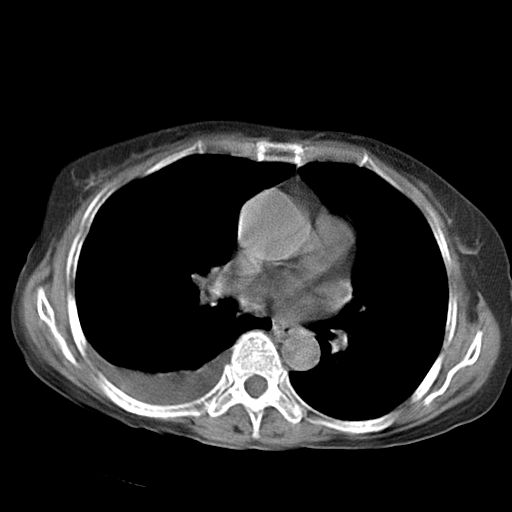

以下是引用dyqct在2006-12-7 21:08:00的发言:[br]考虑:1、肝内外胆管多发性结石伴肝左叶外侧段肝萎缩;[br] 2、右膈下多发脓肿;[br] 3、右侧少量胸腔积液、斜裂积液;[br] 4、左肾囊肿。

以下是引用拾荒者在2006-12-7 21:44:00的发言:[br]肝内外胆管多发结石,右膈下多发脓肿,右胸膜腔及叶间裂积液,左肾囊肿。[br] [br]